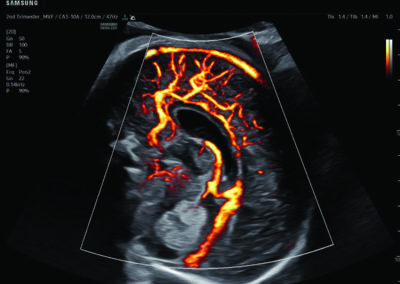

Comprehensive, advanced and expert MFM care for high-risk pregnancies

- Fetal anomalies

- Intrauterine growth restriction